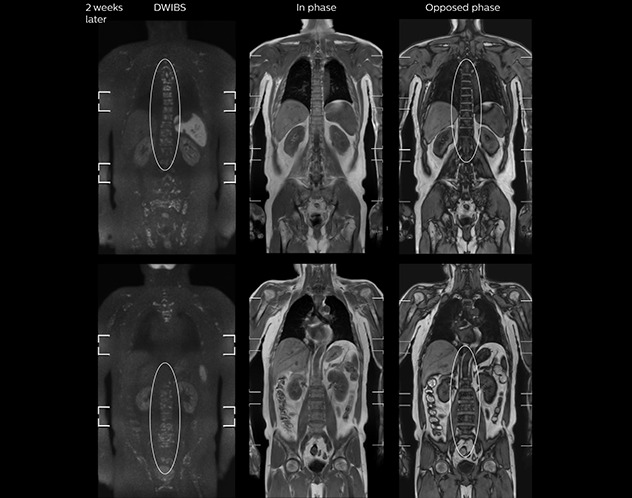

“mDIXON FFE allows us to quickly get information we need to assess the presence of fat. That gives us more information when we need to diagnose bone lesions, and when we are asked to judge fat-containing lesions such as hepatocellular or renal carcinoma,” Dr. Nobusawa says. “The mDIXON fat images can help us to differentiate fatty bone marrow from bone lesions. This is especially useful in elderly people, who tend to have fattier bone marrow. The water images provide a high signal-to-noise ratio in the intestinal canal, which is valuable for visualizing lesions in the colon,” he says.

Kawasaki Sawai Hospital’s whole body protocol also includes an mDIXON FFE sequence. Because mDIXON provides images for four contrast types – water only, fat only, in-phase and out-of-phase – from a single acquisition, it is useful in many ways.

“In-phase and out-phase sagittal T1-weighted FFE images help us to visualize and further characterize bone lesions such as metastasis and bone-marrow hyperplasia that have high signal on DWI. These images are also used throughout radiotherapy, to monitor changes in the fatty bone marrow.”